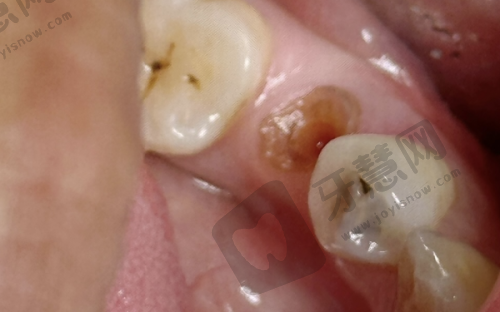

♥实例一:55岁王先生·韩国登腾种植体修复后牙

王先生因牙周病拔除右下后牙2颗,牙槽骨宽度4.5mm,骨量基本充足。选择南庄拜博口腔的韩国登腾种植体 + 全瓷冠方案,总费用16800元(含术前CT和术后护理)。采用数字化导板精细植入,手术时间40分钟,术后当天即可进食软食。3个月复查时,种植体骨结合良好,咬合力修复至自然牙的80%,王先生表示“现在啃排骨都没问题,比活动假牙舒服太多!”